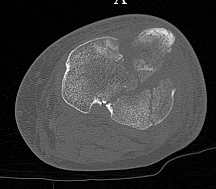

[Ortho] перелом проксимальной тибии + вывих бедра

Серия КТ сканов в аппарате